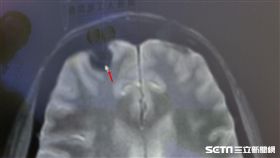

「抽搐、猛吐舌」 竟腦長「鐘乳石」

60歲林姓女患者,晚上在家突然發生癲癇,出現上半身抽...

2019/06/11 08:35